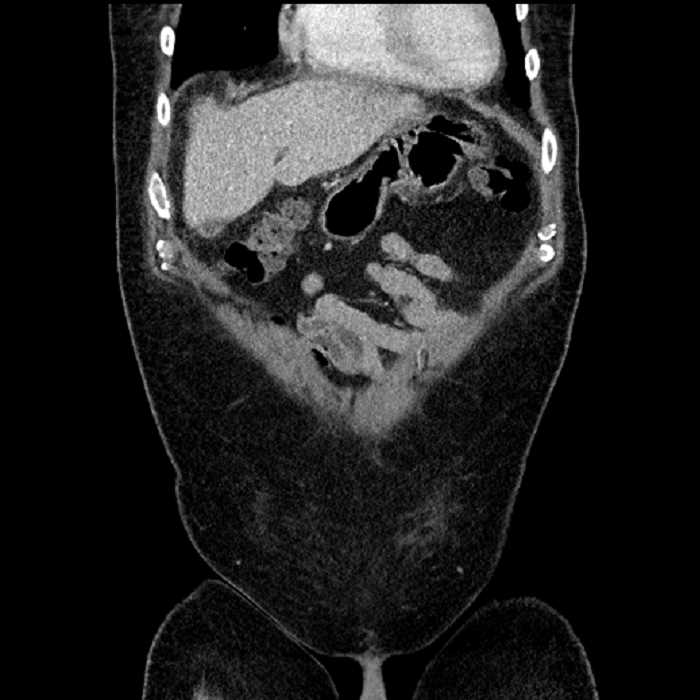

• Large fluid density structure in hepatic segments 7 and 8 measuring 10 x 7 x 7 cm with internal septation and circumferential ill-defined low density compatible with edema

• Peripherally enhancing subcapsular collections along the anterior margin of the left hepatic lobe measuring 3 x 1 cm and 2 x 1 cm

• Clearly marginated fluid density structure in segment 7 and several other scattered tiny hypodensities, which likely represent cysts

• Mild mural thickening of a segment of the sigmoid colon with adjacent fat stranding and a 1.5 cm fluid and gas collection along the tip of an inflamed diverticulum

• Loss of the normal fat plane between this collection and adjacent loops of small bowel, which demonstrate mural thickening

Acute sigmoid diverticulitis complicated by a small contained perforation and a large abscess in the right hepatic lobe. Additional small subcapsular abscesses along the anterior margin of the left hepatic lobe.

Additionally, loss of the normal fat plane between the peridiverticular collection and adjacent thickened loops of small bowel raises the potential for an enterocolonic fistula.

• The classic CT imaging appearance is a double target sign with internal low density surrounded by an internal enhancing rim (capsule) and a low density external rim (edema)

Hepatic abscess showing the double target sign with low density internally surrounded by a thin inner enhancing rim (red arrow) and ill-defined outer low density rim (yellow arrow). Blue arrow indicates an internal septation. Red arrows: additional smaller subcapsular abscesses. Red arrow: focal contained perforation associated with diverticulitis.